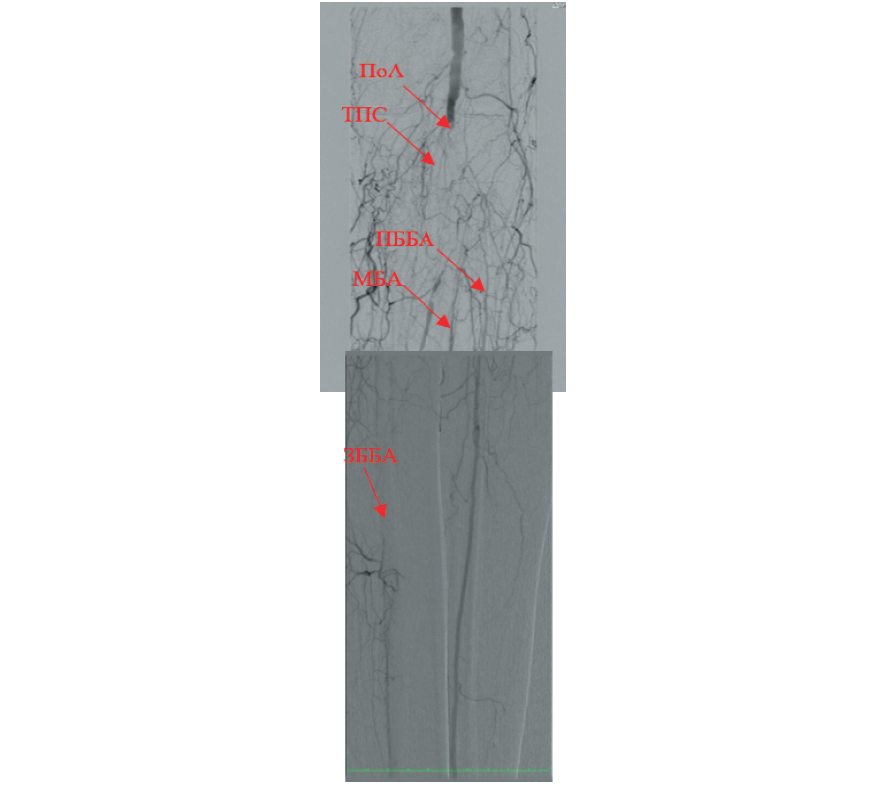

Диагностическая селективная ангиография: окклюзия ПоА ниже уровня щели коленного сустава, окклюзия ТПС, окклюзия МБА и ЗББА на всем протяжении, ПББА (рис. 3).

Рис. 3. Результат диагностической субтракционной ангиографии пациента Б., 69 лет, с сахарным диабетом и критической ишемией нижних конечностей. Выявлены окклюзии в дистальном сегменте подколенной артерии (ПоА); окклюзия тибиоперонеального ствола (ТПС), малоберцовой артерии (МБА), задней большеберцовой артерии (ЗББА), передней большеберцовой артерии (ПББА).